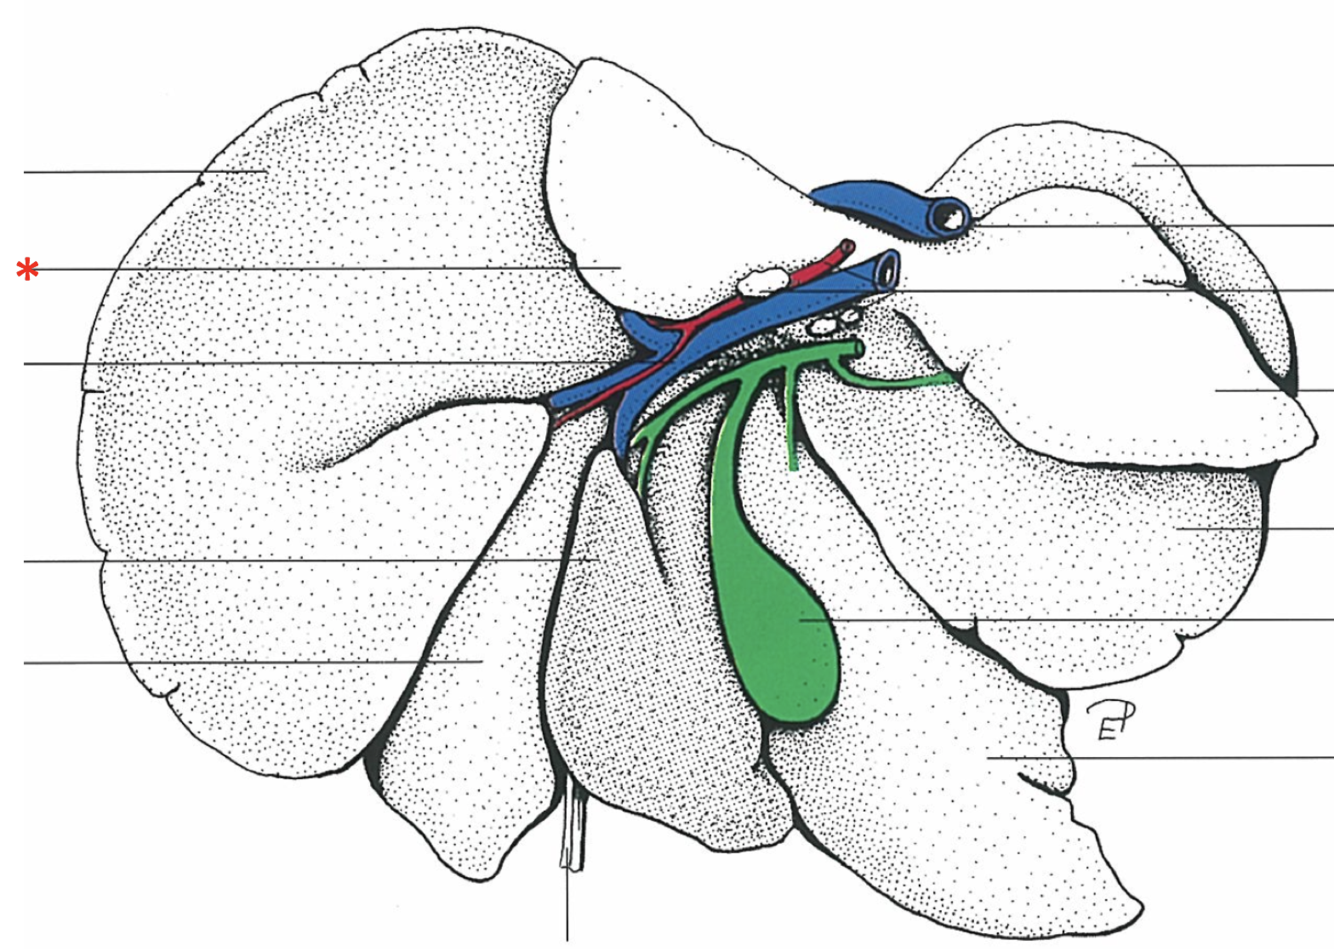

Porta hepatis

- With v. portae et a. hepatica

Lobus caudatus

Lobus quadratus

Lobus hepatis sinister medialis

Lobus hepatis dexter medialis

Lobus hepatis dexter lateralis

Proc. caudatus

V. portae

Proc. papillaris

Lobus hepatis sinister lateralis

Impressio renalis

Liver of a Cat

What is shown? Give the Aspect

Liver of a Cat

Fascies visceralis